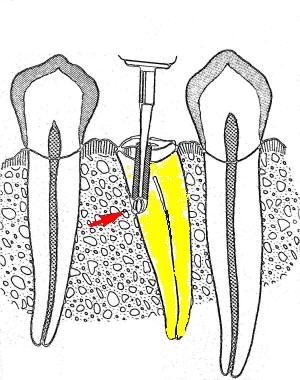

4- Grado de deterioro de la corona clínica por exposición

a caries o trauma

Grandes obturaciones cercanas a la cámara pulpar,

en la mayoría de las veces es directamente proporcional al

grado de calcificación de la cámara y de los conductos

radiculares. Ver primer imagen derecha

La falta de la corona clínica puede ser causa de

perforaciones accidentales. Ver segunda imagen derecha

La utilización sistemática de la radiografía periapical

pre-operatoria evitaría estos accidentes que suelen ser

comunes durante la práctica clínica.